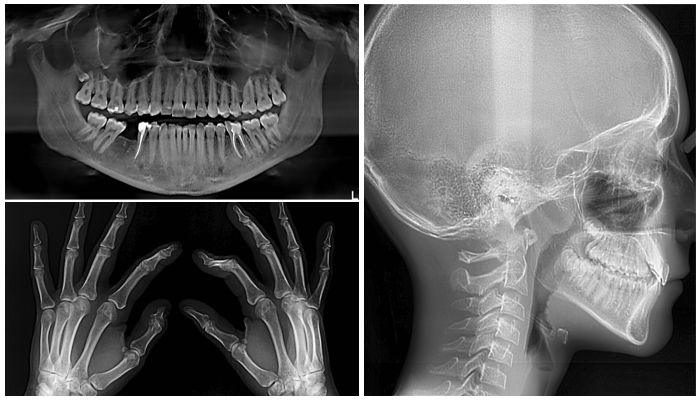

- снятие снимков и изучение диагностических моделей челюстей;

- рентгеновские методы — ортопантомограмма, телерентгенограмма в боковой проекции, рентген кистей рук для определения стадии развития челюстей.